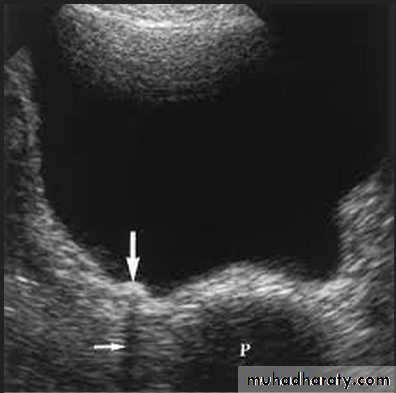

Typically, a cyst containing a clear fluid has few if any echoes (anechoic =black ) ,

Tissues such as liver and spleen give a picture with rather homogeneous small echoes due to the fibrous interstitial tissue (hypo echoic , isoechoic or hyper echoic = gray scale spectrum ) ,

Metals or Calcium in the bone and stones ( echogenic = white ) .